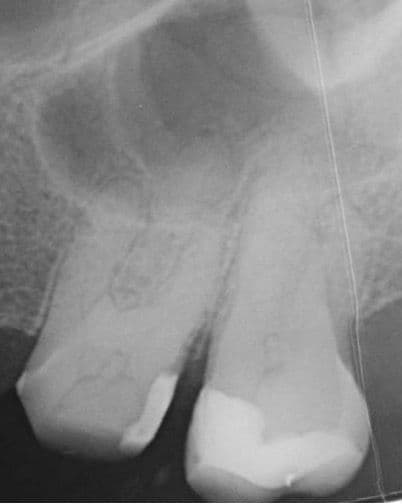

Tedavi esnasında dişin meziobukkal kanalının apikal üçlüsünde alet kırığı meydana geldi. İlgili kırık alet bypass yapılmaya çalışıldı ancak başarılı olunamadı ve kanalda basamak oluştu. Dişin vital olduğu da göz önünde bulundurularak kök kanalları doldurularak dişin takibine karar verildi (Şekil 2).

(Şekil 2) 2023 Mayıs Post-Op radyografi